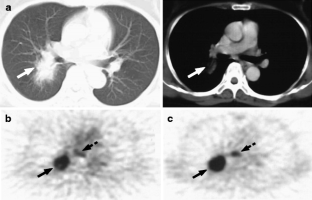

Fig. 3